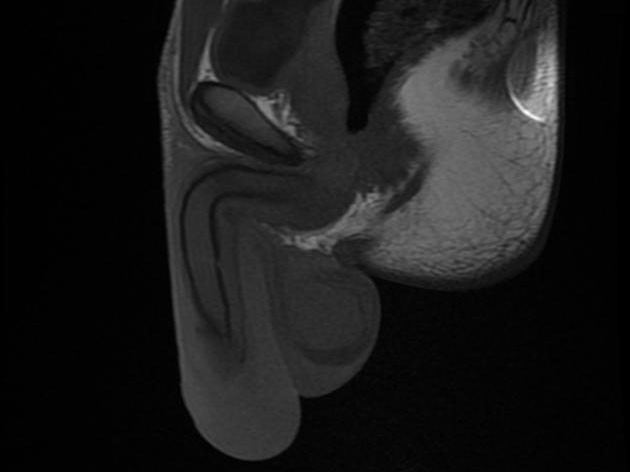

And in case you have never seen what it looks like before, here are some images: (The broken penis becomes bent, deformed, swollen and engorged with blood from internal bleeding into the penis) It’s not a great sight at all. So please, dear entanglement crew, Let’s be careful.”